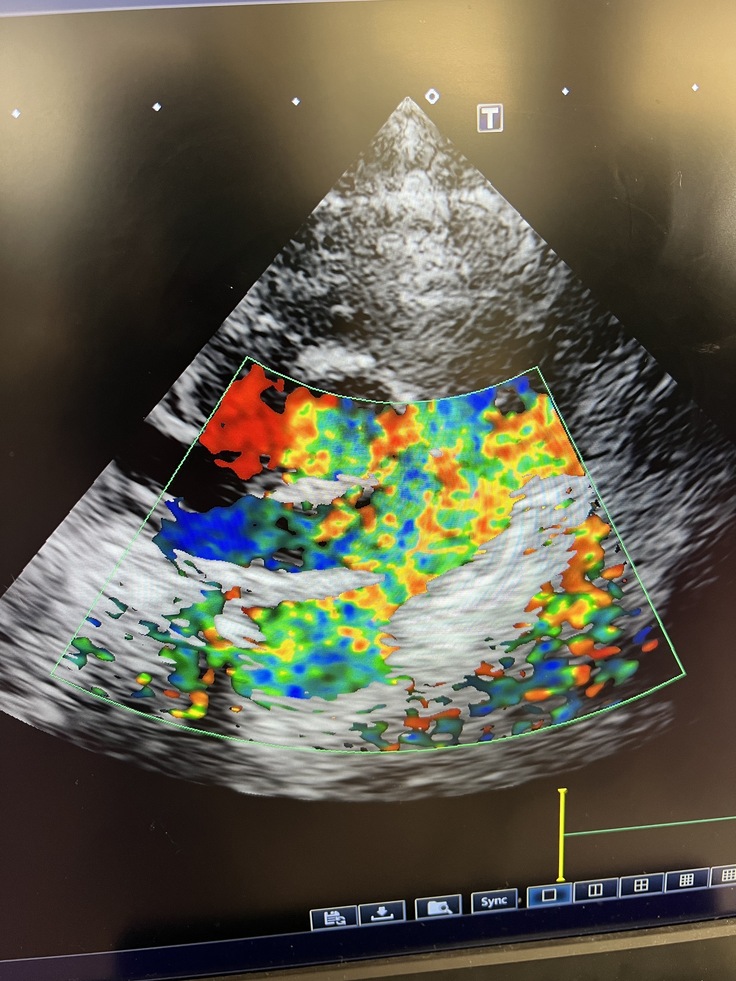

↑まる子のエコー

エコー検査では肺動脈に通常では赤色と青色は見られても良いのですが、この子は出てはいけない色(黄色や緑色)が見られ明らかに異常な状態です。